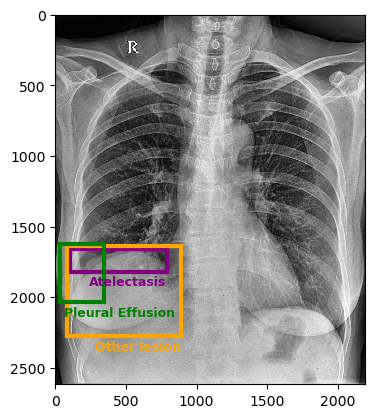

![]() |

The VinDr-CXR dataset includes 15,000 images within its training set, with labels manually defined by a team of radiologists. Figure 3 presents sample images from this dataset. The dataset includes 22 local labels represented by bounding boxes surrounding abnormalities, and six global labels denoting detected diseases. The images are provided in the Digital Imaging and Communications in Medicine (DICOM) format, accompanied by relevant DICOM tags such as patient sex and age. Primarily consisting of posterior-anterior (PA)-view chest X-rays, the dataset excludes non-relative X-rays from other body parts [23].